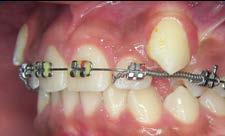

Tratamiento de caninos retenidos superiores en paciente en crecimiento con clase II división 2. Reporte de caso clínico

Caso clínico

Los caninos retenidos constituyen una alteración eruptiva frecuente, con mayor prevalencia en la arcada superior. Su etiología es multifactorial y puede interferir con el trayecto normal de erupción, comprometiendo la oclusión y la estética.

Objetivo: Corregir una maloclusión Clase II división 2 mediante tratamiento ortodóntico en un paciente en crecimiento con ambos caninos superiores retenidos. Metodología: Se presenta el caso de un paciente masculino de 12 años, en dentición permanente, con perfil convexo, patrón dolicofacial y Clase II esquelética. Se realizó tratamiento ortodóntico sin extracciones. Para la tracción y alineación de los caninos retenidos se emplearon resortes abiertos (open coil springs) para la creación de espacio. Resultados: